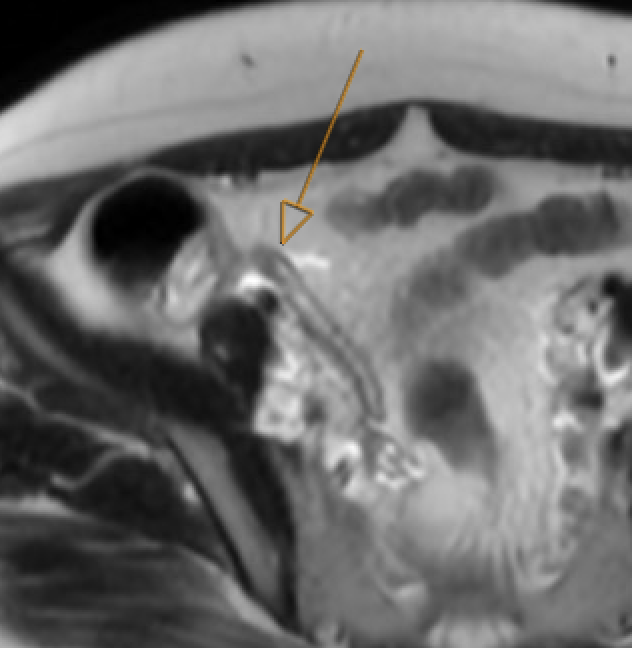

Choledocholithiasis T2-hypointense filling defect in bile duct on MRCP. Obstructive: upstream dilatation, abrupt caliber change. Trace entire biliary system on thin MRCP/T2W

MRCP showing T2-hypointense filling defect in common bile duct consistent with choledocholithiasis

Choledocholithiasis: T2-dark filling defect (arrow) on MRCP

GB neck and cystic duct are blind spots. Pneumobilia can mimic calculi (nondependent, blooms on GRE). Crossing vessel on coronal MRCP can mimic filling defect — check axial reformats